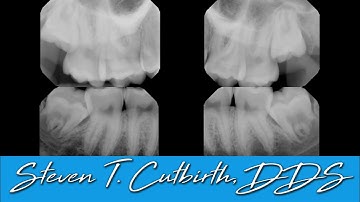

Sectioning Extraction and Bone Grafting - Dental Minute with Steven T. Cutbirth, DDS